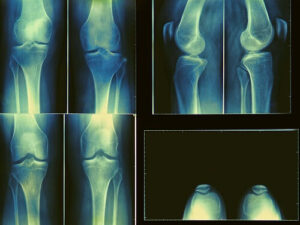

- рентгенографического исследования;